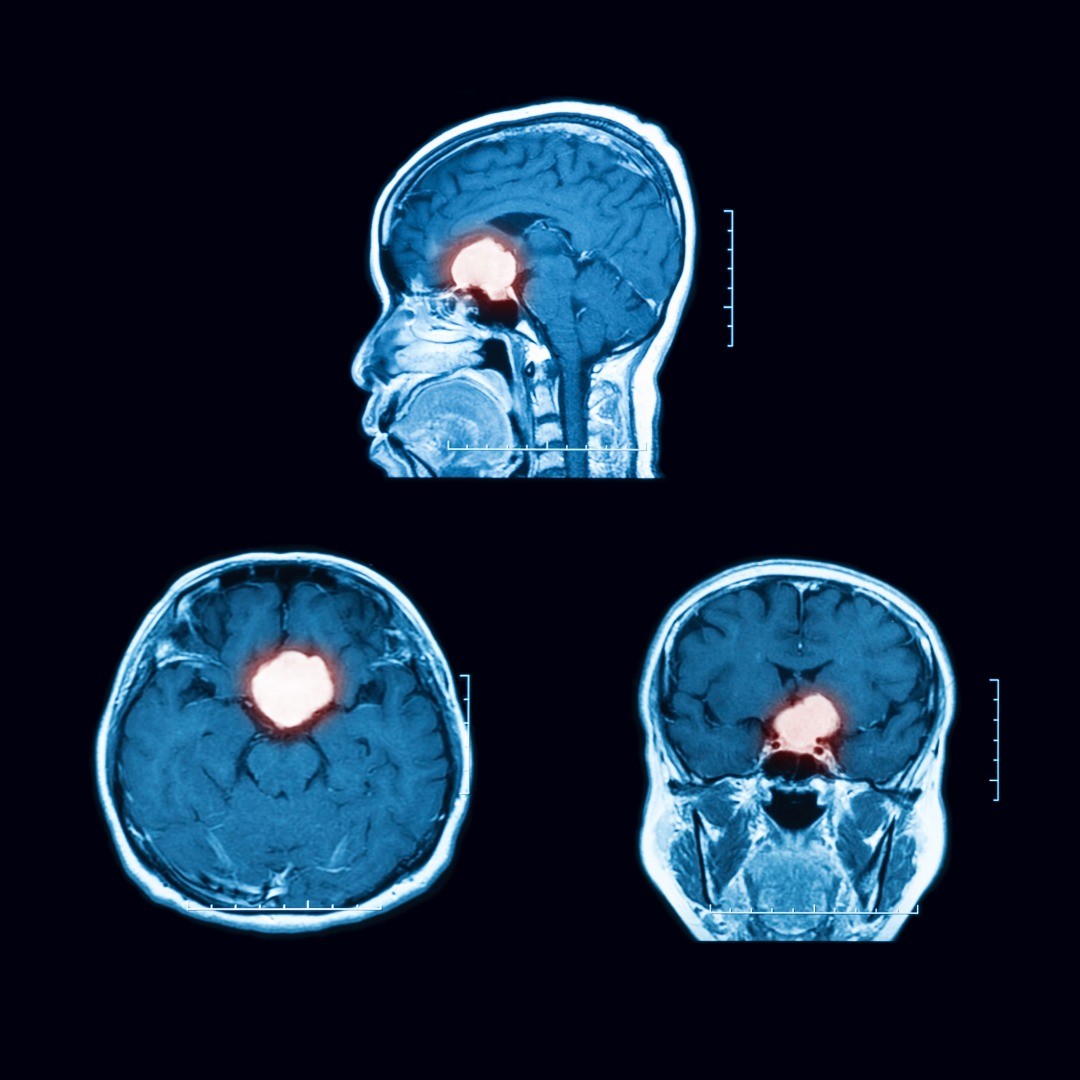

General anesthesia is used and our patients are typically hospitalized for 2-5 days after the procedure for close monitoring. After release, you will be able to return to work in 3 to 6 weeks. A follow-up MRI scan will help assess the success of your surgery.

We are always at the forefront of innovative techniques in order to provide you with a superior experience. If transsphenoidal surgery does not completely resolve your cancer, we have follow-up tools such as the Gamma Knife, a form of stereotactic surgery, in our arsenal to help in your battle with cancer.